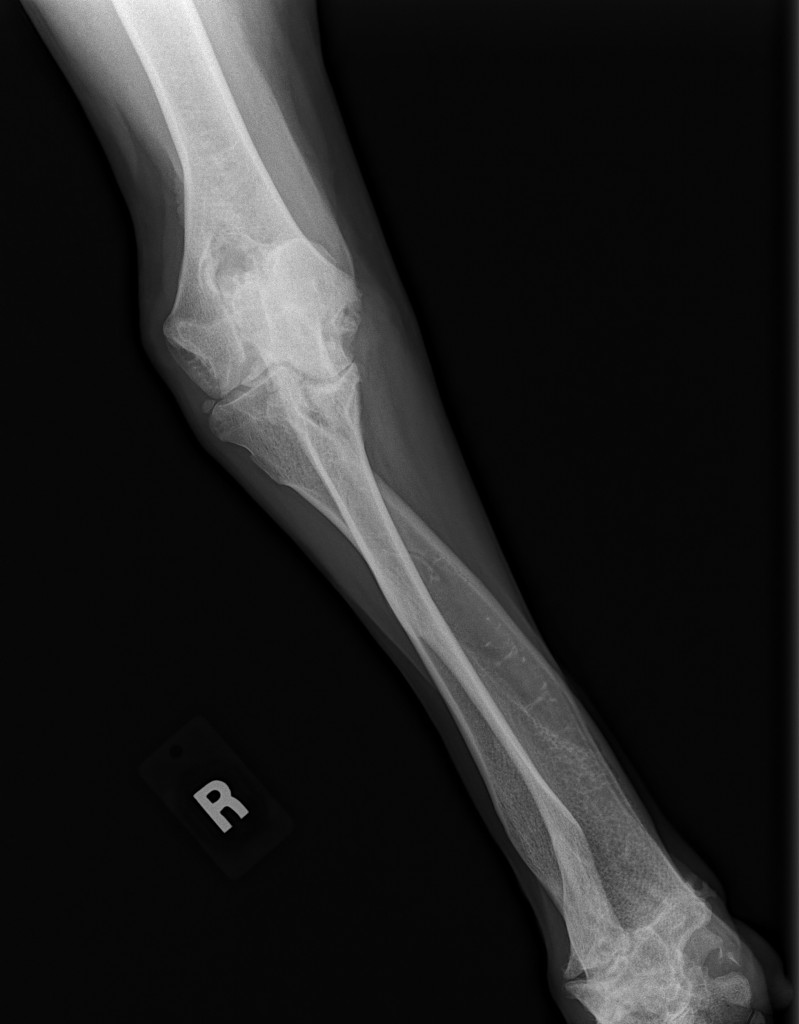

Sean has been diagnosed with a retro-peritoneal liposarcoma.

The current size of his mass is 8.2 cm x 10 cm x 21 cm. This is an extremely RARE cancer – less than 1%.

To further complicate matters, this mass has herniated down into his thigh and groin severely compromising his ureter and femoral nerve. He has had three CT scans of which his latest has shown that to date his chest remains clear of metastasis and his lymph nodes are not enlarged. His MRI has shown that his case is extremely complicated and the surgery he shall specifically require, scheduled for March 23rd has ONLY ever been done twice before by the two expert surgical oncologists assigned to him.